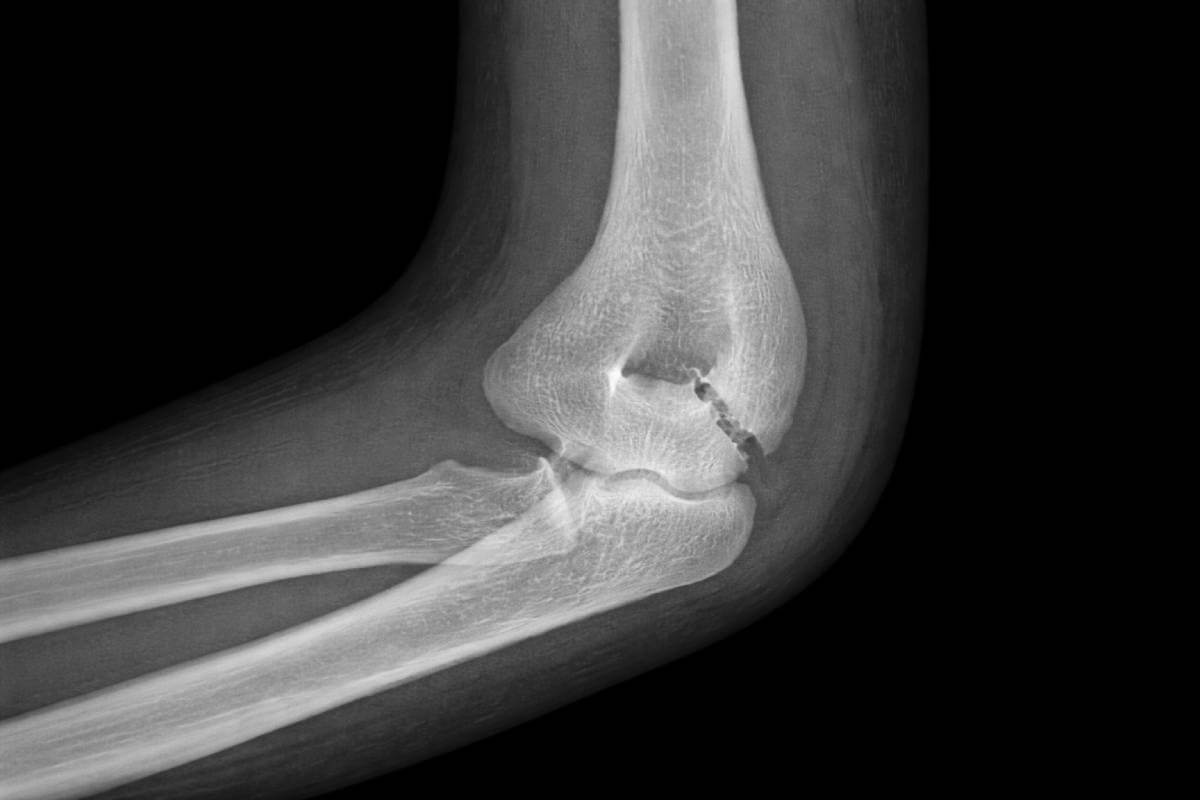

La riabilitazione dopo una frattura del gomito riveste un ruolo fondamentale per recuperare mobilità, forza e funzionalità dell’arto.